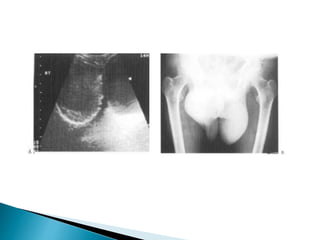

 Sonographically it is seen as an anechoic area

partly surrounding the testicle

considerable calcification of the tunica .

 Following trauma a haematocele will exhibit